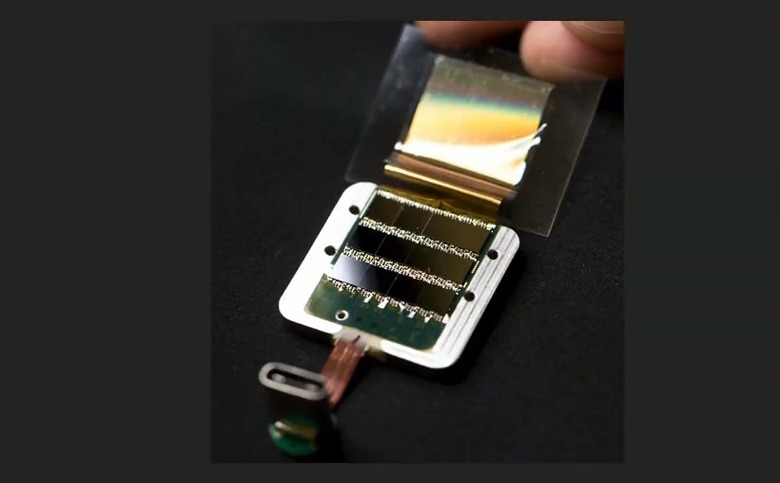

According to the article, its bundles of flexible threads are about one quarter the diameter of a human hair, implanted using needles to avoid blood vessels on the brain's surface. Then the embedded sensors capture information and send it to a receiver (the chip above) on the surface of the skull. From there it transmits wirelessly — Elon Musk said it could Bluetooth the information to your skull. Right now implantation requires drilling holes, but researchers hope in the future they can use lasers to avoid "unpleasant" vibration.

According to Musk, its current v1 4x4mm chip is capable of 10,000 electrodes with "read and write" capability, which he says is more than 1,000 times the number of the best deep brain interface currently available for Parkinson's treatment.